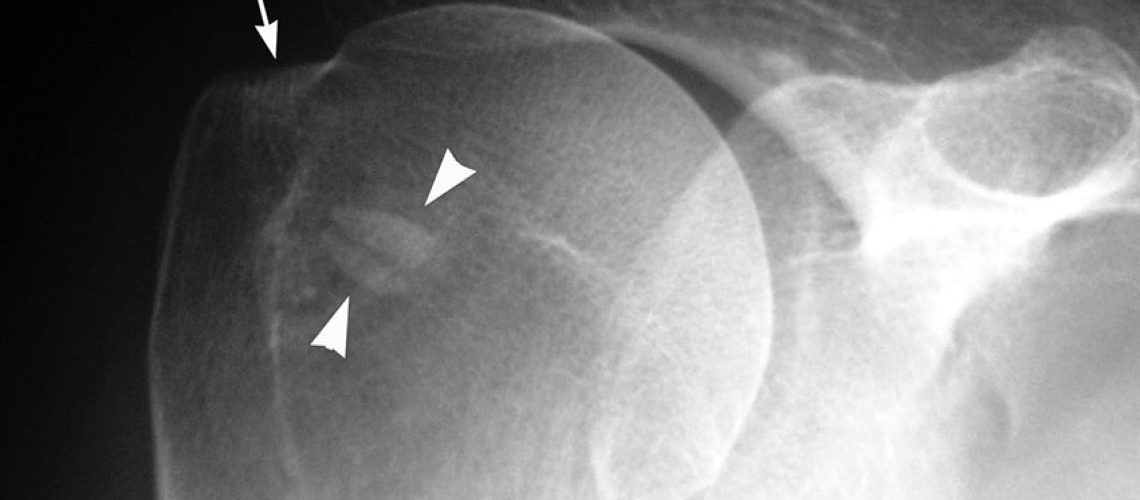

CALCIFICACIÓN EN EL TENDÓN

Una de las causas mas comunes de dolor en el hombro son las calcificaciones. Mas frecuentes en mujeres entre 40 y 50 años y suelen aparecer en el brazo dominante, aunque no siempre es así.

También llamada tendinitis calcificante, son depósitos de calcio sobre los tendones del hombro. El calcio provoca la irritación de los tendones del manguito rotador, lo que puede causar dolor agudo. Normalmente ocurren en el supraespinoso, aunque también puede darse en el infraespinoso o en el tendón subescapular.